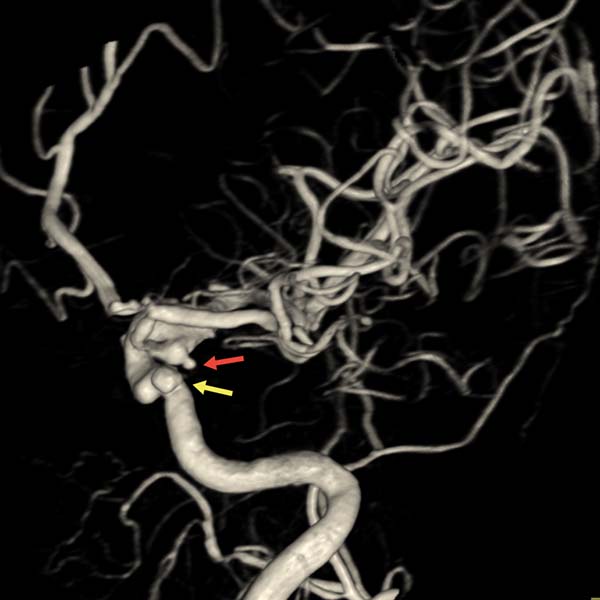

▲右颈内动脉3D-DSA显示两个动脉瘤

后交通动脉瘤不规则

瘤颈处发出胚胎型大脑后动脉

瘤顶端可见子瘤(红箭头)